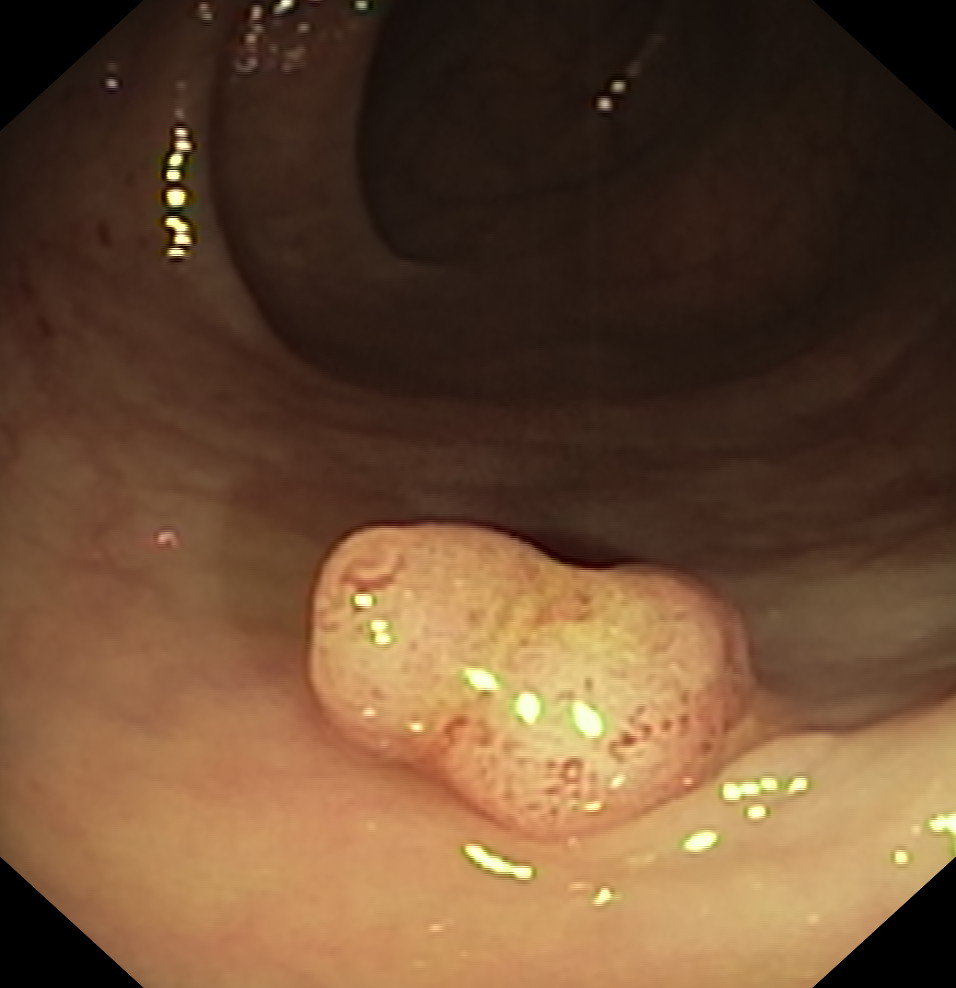

Polipy